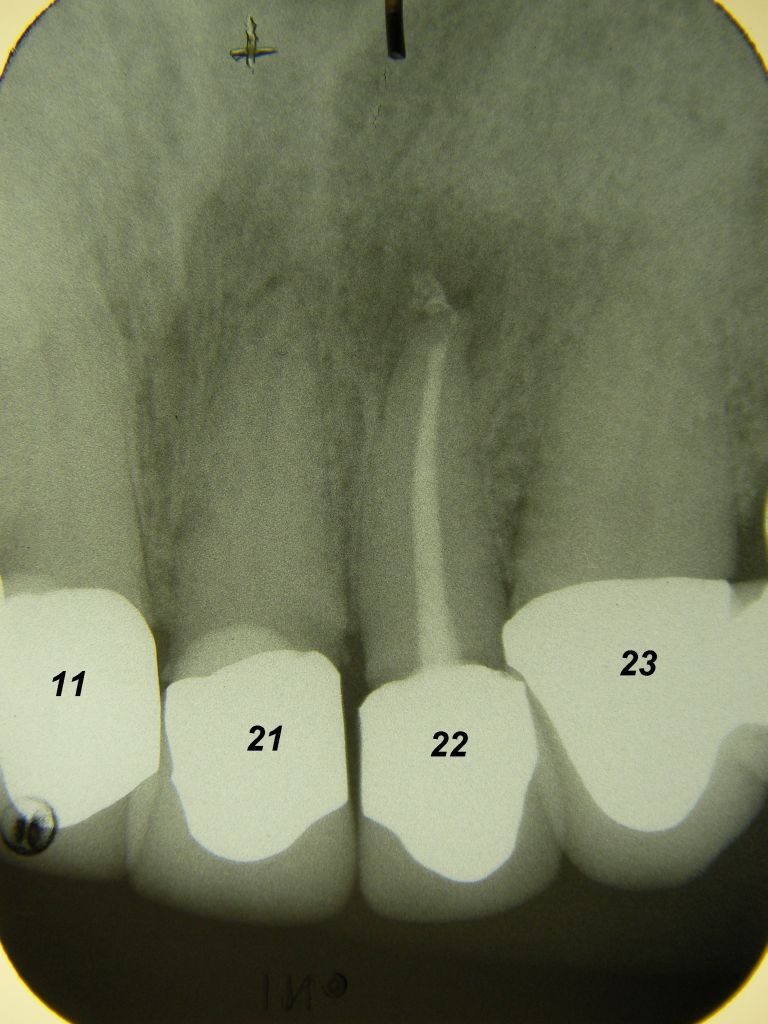

Das etwas dunkle Röntgenbild links(6/2003) zeigt diverse Probleme. Hier interessiert, daß der Zahn 22 (sprich: "zwei", "zwei") am 28.10.05 Schmerzen bereitete, weil der Zahnnerv unter Eiterbildung abgestorben war. Es brauchte 3 medikamentöse Einlagen, bis der Zahn ruhig war und am 18.11.05 eine Wurzelfüllung und einen Titanstift in den Wurzelkanal bekommen konnte. Bei der anschließenden Röntgenkontrolle rechts fiel der schlechte Randschluß der Krone 22 auf. |

Weil auch die anderen Schneidezahnkronen (12-22) durch Randreparaturen und den schlechten Randschluß erneuerungsbedürftig aussahen, wurden 4 Einzelkronen geplant. Vorher hieß es aber noch, die schlechte Wurzelfüllung im Zahn 12 (Röntgenbild links) besser zu machen. Hierfür wurden am 17.2.06 die alten Kronen 11 und 12 entfernt. Rechts das Bild nach Entfernung von alten Füllungen und Karies. | |

Links nach Wurzelfüllung beim Einpassen des Titanstiftes. Rechts dann der schon provisorisch beschliffene Amalgamaufbau im Zahn 12. |